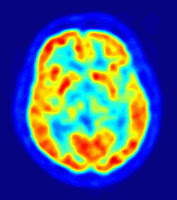

Промените в нивата на серотонинът в мозъка може да повлияе на настроението. Някои антидепресанти оказват влияние върху действието на серотонина, т.е. те се използват за лечение на депресия.

Около 80% от общия серотонин в тялото ни се произвежда в чревният и стомашен тракт, в клетки наречени ентерохромафини- и така хормонът регулира чревните движения. Останалото количество се синтезира в серотонинергични неврони в централната нервна система.